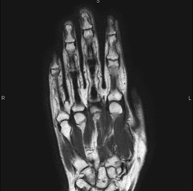

Exploració per a l'estudi de lesions en els tendons, els músculs i les articulacions. Molt útil per a la valoració de petites fractures inadvertides, lesions de lligaments i processos inflamatoris i degeneratius (artritis i artrosi). La durada aproximada és de 20 minuts. No utilitza radiació ionitzant. - RM de Mà / dits

Exploració per a l'estudi de lesions a tendons, lligaments i petites articulacions. És la prova que permet diagnosticar millor les capsulitis freqüents per traumatisme, l'artrosi i els trencaments de tendons. La durada aproximada és de 20 minuts. No utilitza radiació ionitzant. - RM de Malucs